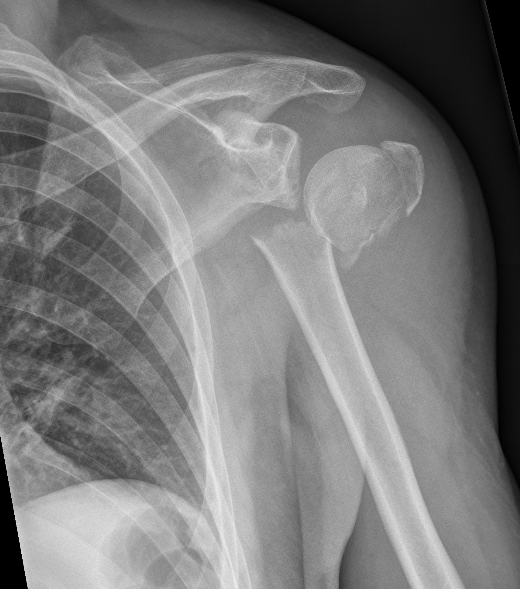

The treatment of shoulder fractures requires precise diagnostics and individually tailored therapy. In many cases - especially with stable, non-displaced fractures - conservative treatment with immobilization and subsequent physiotherapy may be sufficient. In the case of more complex fractures, displacements or joint involvement, surgery is often necessary to restore anatomy and function. In these cases, the fracture is repositioned (reduced) and fixed with plates and screws.

Today, modern surgical procedures allow for gentle treatment with plates, screws or - in the case of very serious complications - a joint replacement. The aim is always to restore mobility and weight-bearing capacity to the shoulder as quickly and safely as possible.